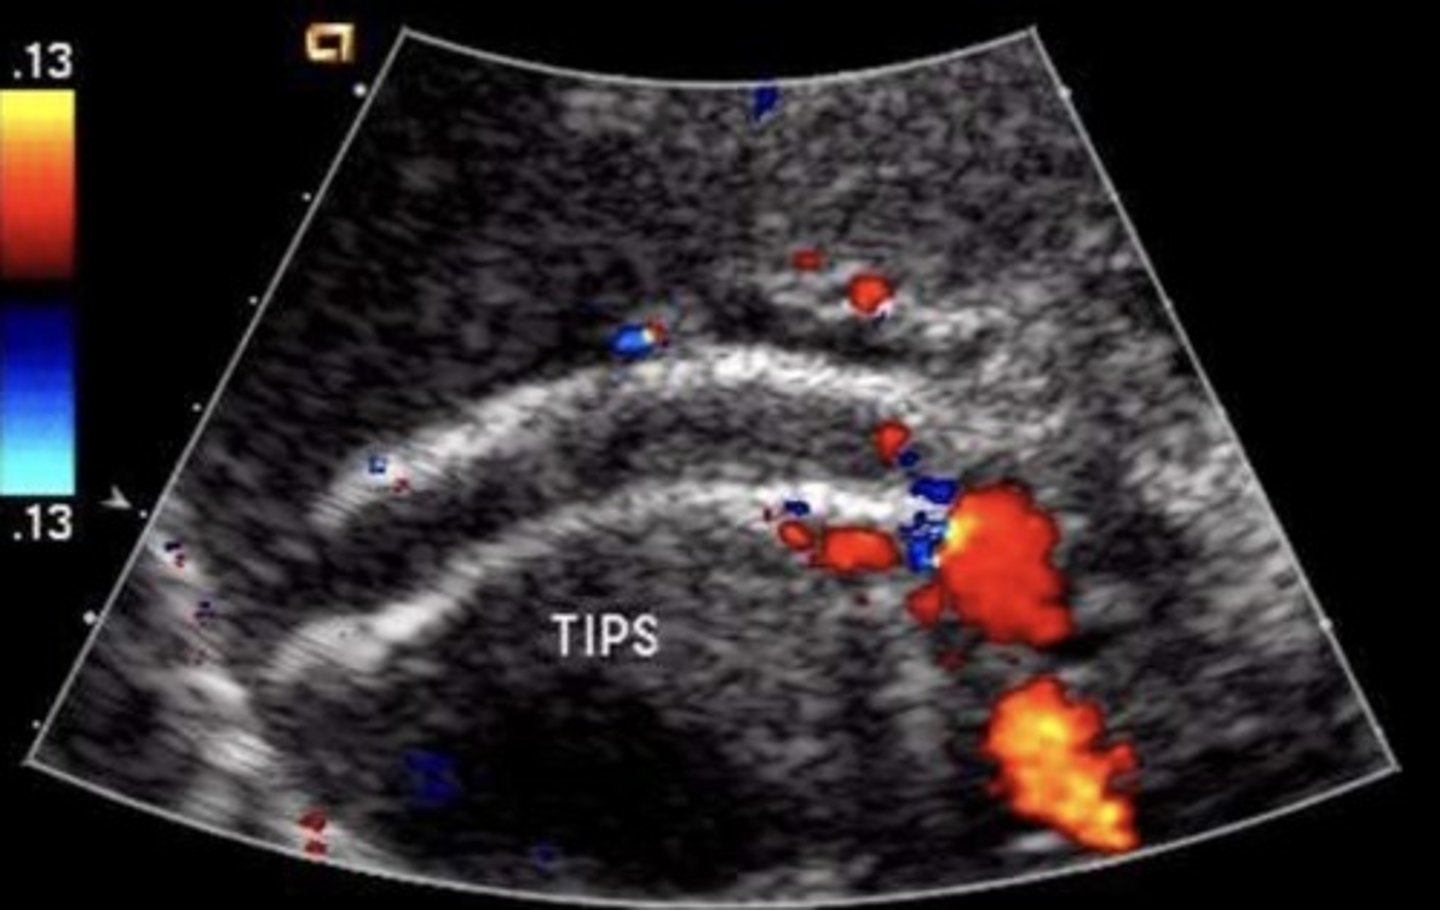

TIPS Shunt

Stent between portal vein & hepatic vein

(commonly right portal vein and right hepatic vein)

TIPS Shunt Normal Findings

No focal aliasing

Hepatofugal flow in portal veins beyond stent

TIPS Shunt Abnormal Findings

Focal aliasing

Velocity changes

Antegrade flow in right & left portal veins

Retrograde flow in hepatic vein

Developing ascites or collaterals

TIPS Shunt Occlusion Findings

Hepatopetal flow in right & left portal veins

Hepatofugal flow in main portal vein